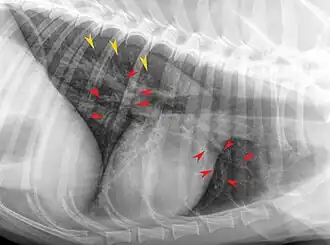

Röntgenaufnahme eines von EBP betroffenen Huskys. Die roten Pfeile markieren einige der verdickten Bronchialwände, die gelben Pfeile interstitielle Verdichtungen.